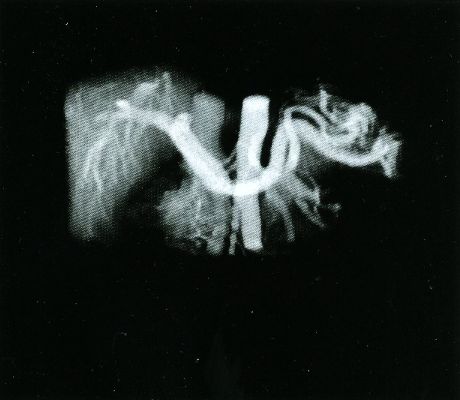

Here are typical examples of VoxelQ displays. These are mostly only windows, not the full screen which is more along the lines of the last block of AcQSim photos.

VoxelQ Multiplanar Reformatting (Axial, Saggital, Coronal, Curved)

VoxelQ Shaded Surface

VoxelQ Volume Rendering

VoxelQ Segmentation

VoxelQ Virtual Endoscopy